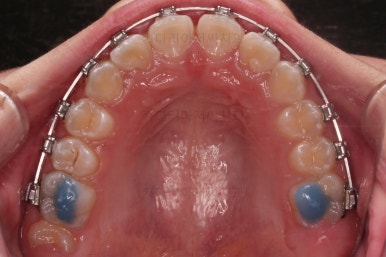

우선 윗니에만 교정장치를 부착했습니다.

성장치료라더니 교정치료? 하실 수 있지만 윗니를 가지런하게 해준 이유는 아래턱을 앞으로 성장시켜줄려니 윗니 앞니가 옥니처럼 가로막고 있어서 아래턱이 앞으로 나올래야 나올 수 없는 상황이었어요.

그래서 앞니의 각도를 먼저 개선해주기로 했죠.

일반적인 교정장치이긴 하지만 그 목적이 달랐던 거에요.

앞니의 각도가 앞으로 살아난 것이 보이실 거에요.

자연스레 과개교합 경향도 개선되어 어금니로 물렸을 때 아래 앞니가 점점 보이기 시작해요.

지금부터 twinblock, 트윈블록 이라는 장치를 이용해 아래턱을 성장시키기로 했어요.